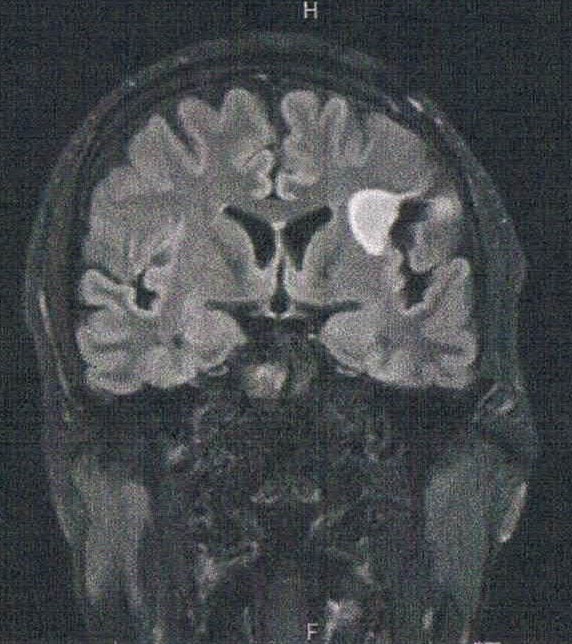

- 初めて前後方向に断面を見た気がするが、2年前の画像と比べると上方向に顕著に大きくなっている。

- 造影剤の有無でも見え方が違うのかもしれないが、上下方向は明らかに大きくなっている。玉子で例えると、直径は変わらないが上下が大きくなっている。

- このペースで大きくなると10年以内には再手術が必要になりそうな予感がする。上方向は除去しても問題ないとは言うが、手術はリスクと痛さがあるのでイヤだなぁ。